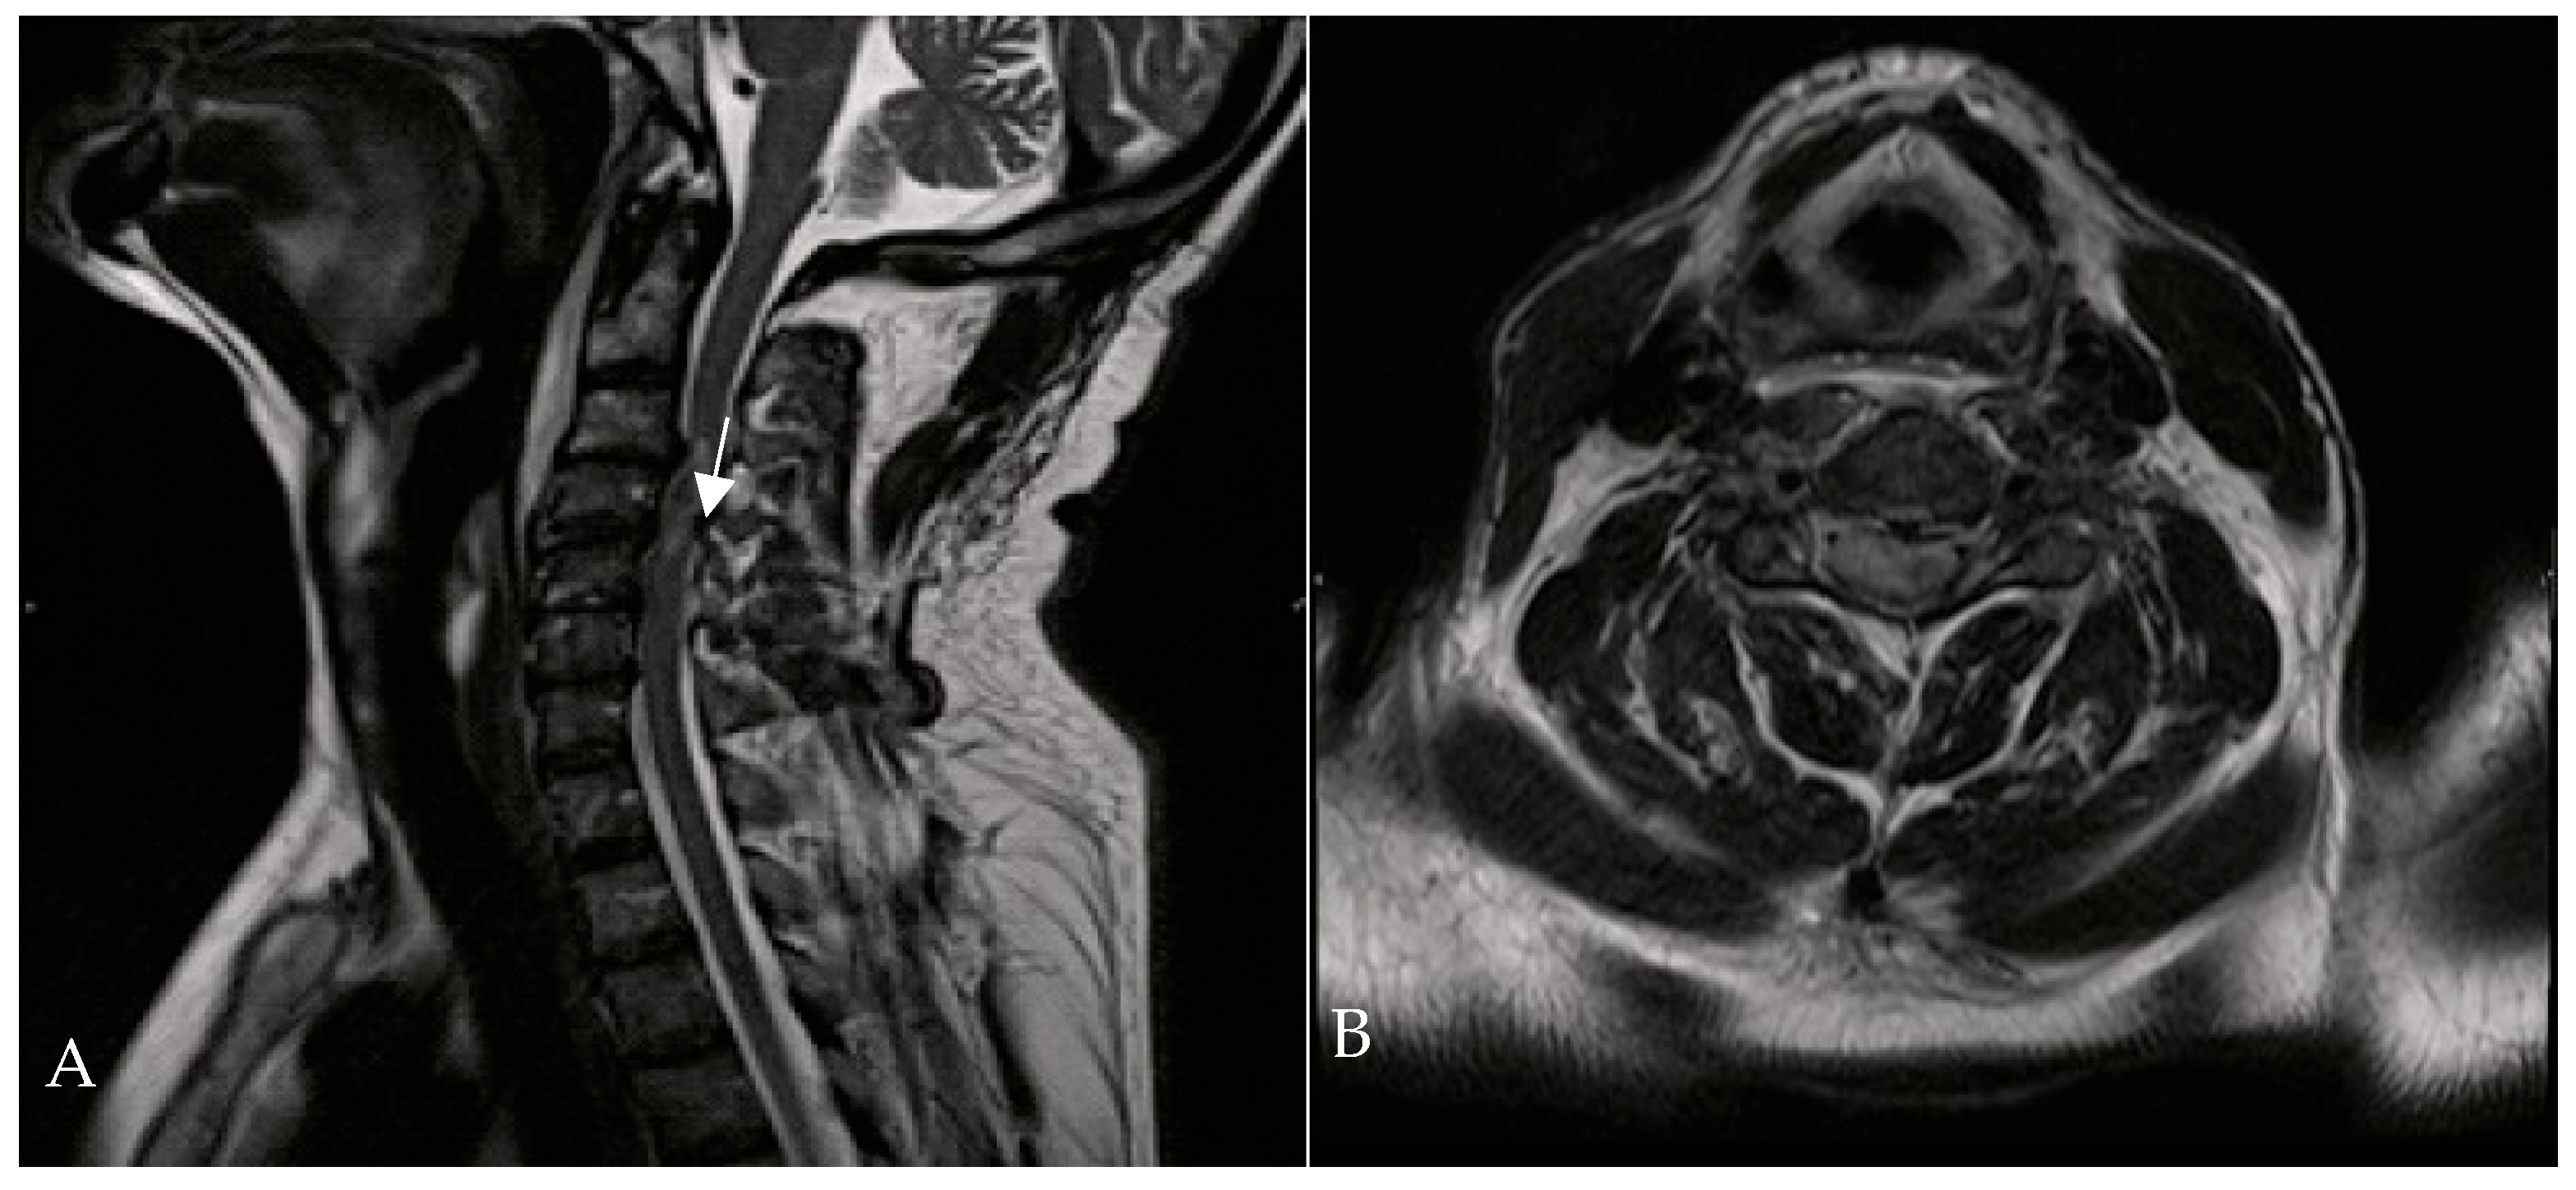

A 67-year-old man was admitted to the Reanimation Unit and Neurosurgery Unit of the University Hospital of Salerno, Italy, after a car accident, presenting with dysphonia, urinary and fecal incontinence, and tetraplegia. Despite these severe symptoms, the patient was awake, co-operative, and retained tactile sensitivity in the extremities as well as facial mimicry. Magnetic resonance imaging (MRI) of the spine revealed hematomyelia because of trauma at the C4 level, with no evidence of vertebral fractures. According to the AIS (ASIA Impairment Scale) score, the neurological examination at the time of admission (Time 0) indicated a neurological level of injury (NLI) at C4, classified as AIS B. The patient was initially treated with intravenous corticosteroids (30 mg/kg bolus, followed by 5.4 mg/kg/h infusion over 23 h). On the second day of admission, HBOT was initiated at 1.8 ATA for 60 min per session (Figure 2).

Figure 2.

Cervical MRI—T1-weighted sagittal (A) and transverse planes (B)—showing hematomyelia (white arrow) at the C3-C4 level without vertebral fractures.